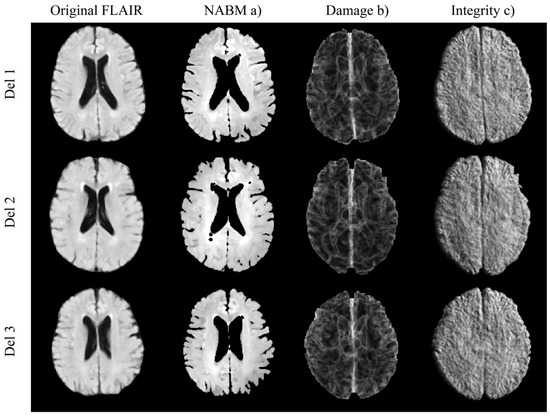

- Bahsoun, M.-A.; Khan, M.; Mitha, S.; Ghazvanchahi, A.; Khosravani, H.; Maralani, P.J.; Tardif, J.-C.; Moody, A.; Tyrrell, P.; Khademi, A. FLAIR MRI biomarkers of the normal appearing brain matter are related to cognition. Neuroimage Clin. 2022, 34, 102955. [Google Scholar] [CrossRef] [PubMed]

- Di Gregorio, J.; Arezza, G.; Gibicar, A.; Moody, A.R.; Tyrrell, P.N.; Khademi, A. Intracranial volume segmentation for neurodegenerative populations using multicentre FLAIR MRI. Neuroimage Rep. 2021, 1, 100006. [Google Scholar] [CrossRef]